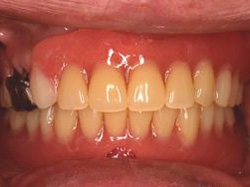

術後(鏡像)術後(鏡像)術後(鏡像) 術後口腔内(正面観)術後口腔内(正面観)術後口腔内(正面観)もう入れ歯は要らなくなりました。 術後レントゲン術後レントゲン術後レントゲン